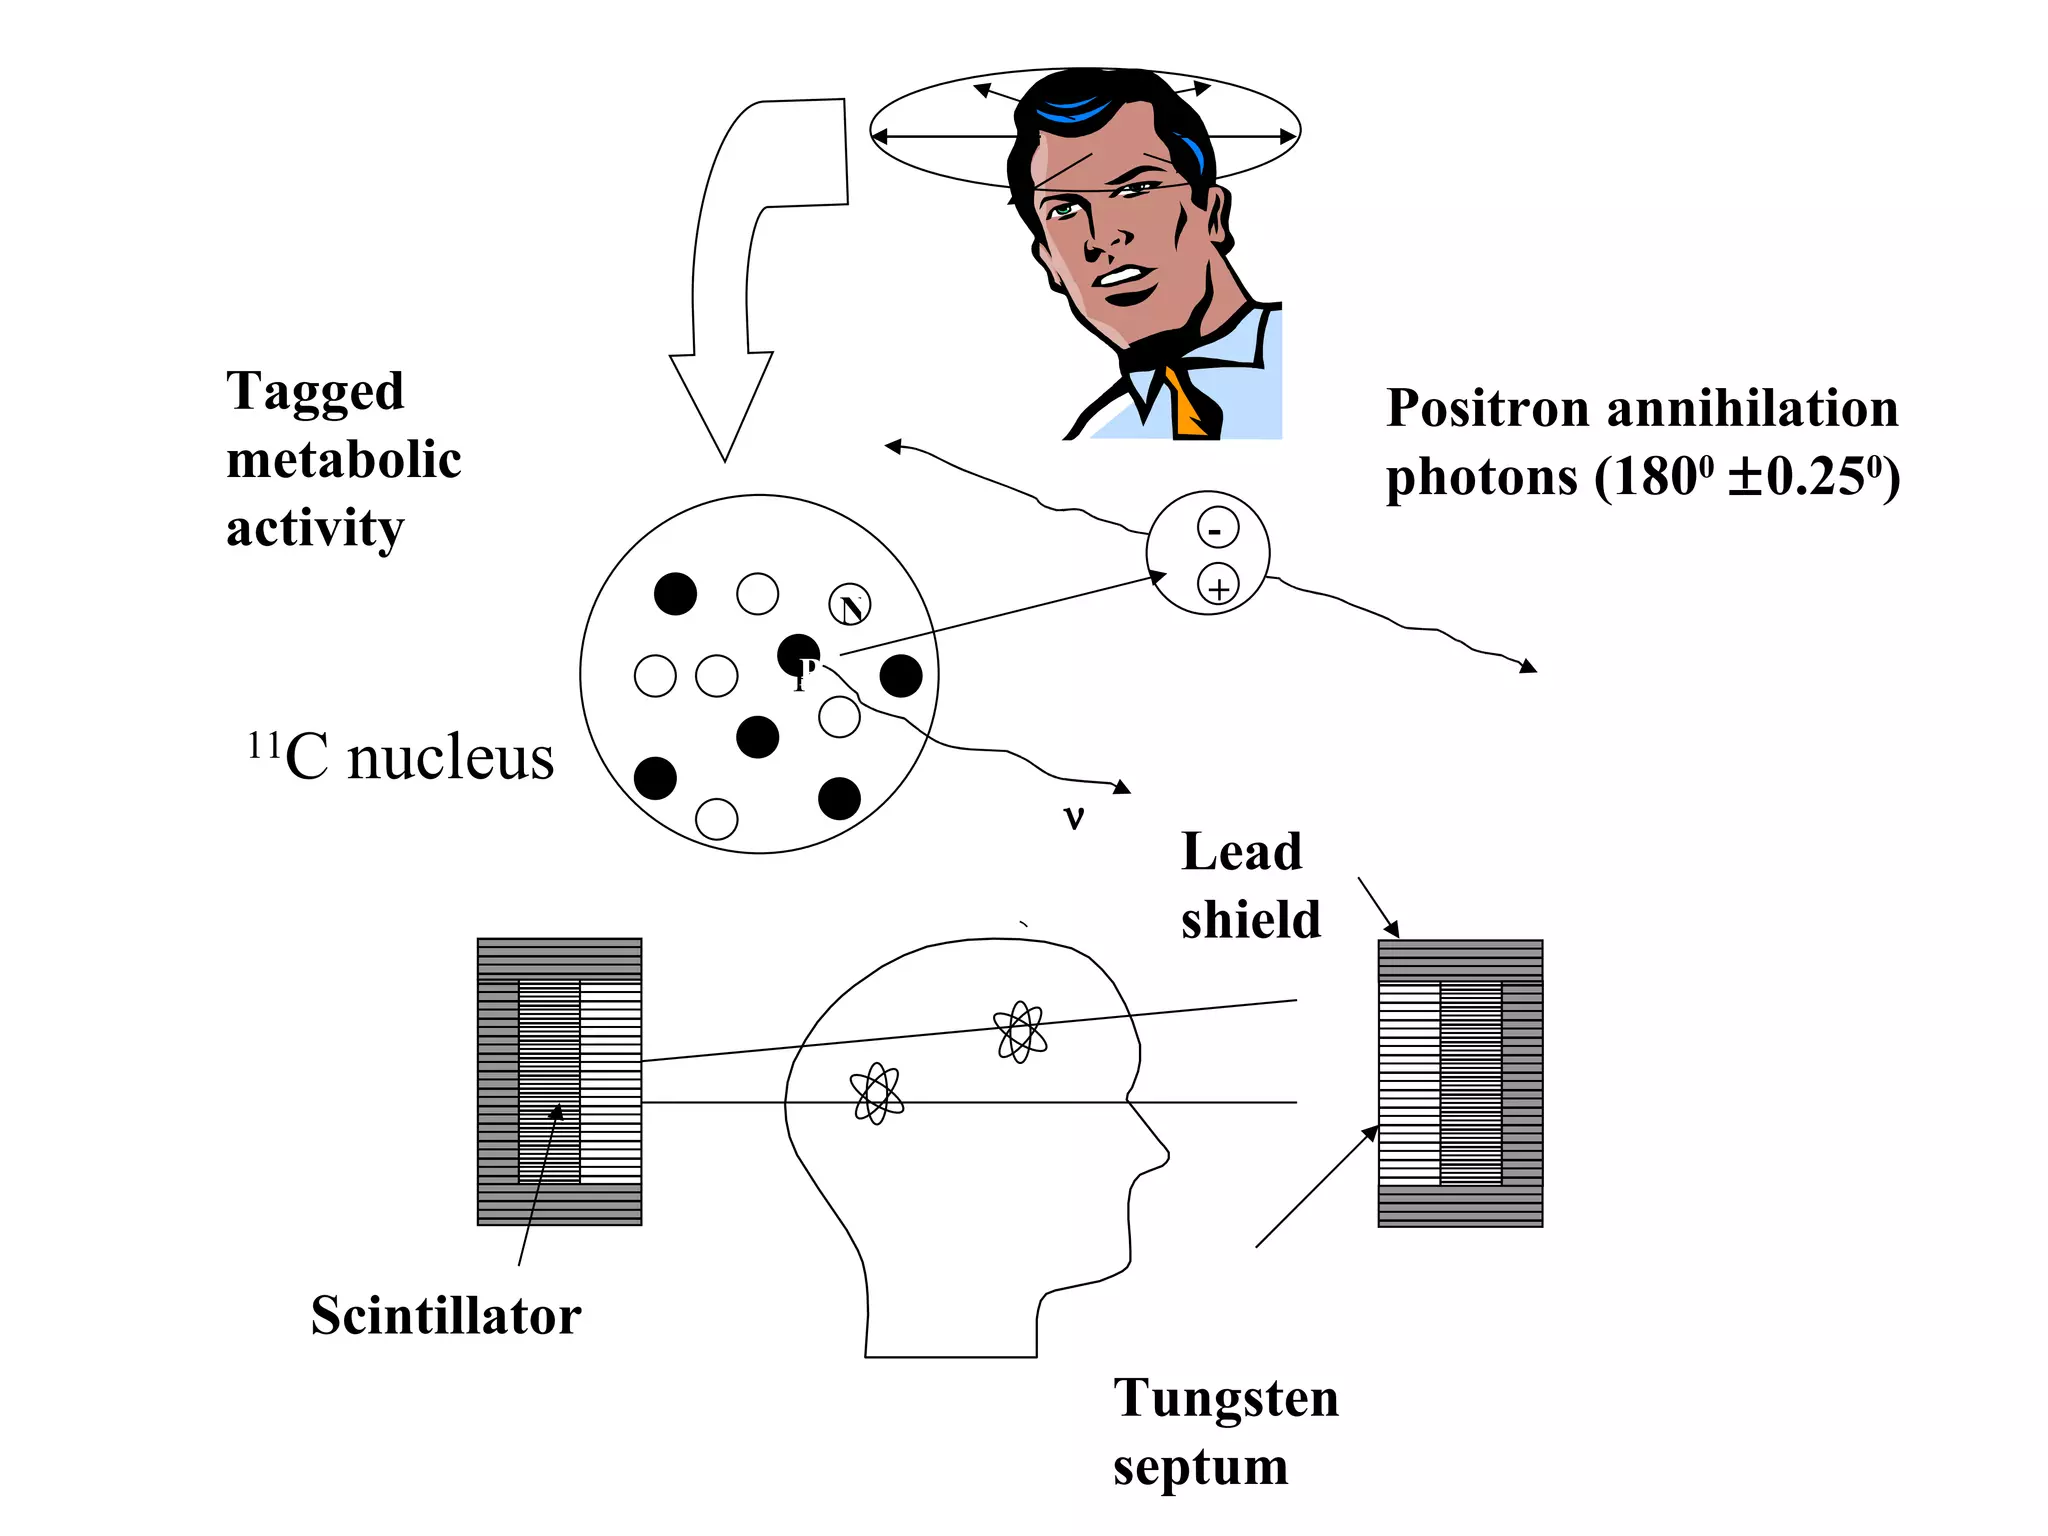

The document discusses various medical imaging modalities including x-rays, computed tomography (CT), and digital mammography. It describes the basic principles and historical development of these technologies, how images are formed, and what types of anatomical features and abnormalities they can detect. Key advances include the development of digital systems that allow image manipulation and remote consultation. While promising, digital mammography still faces challenges around resolution and cost.